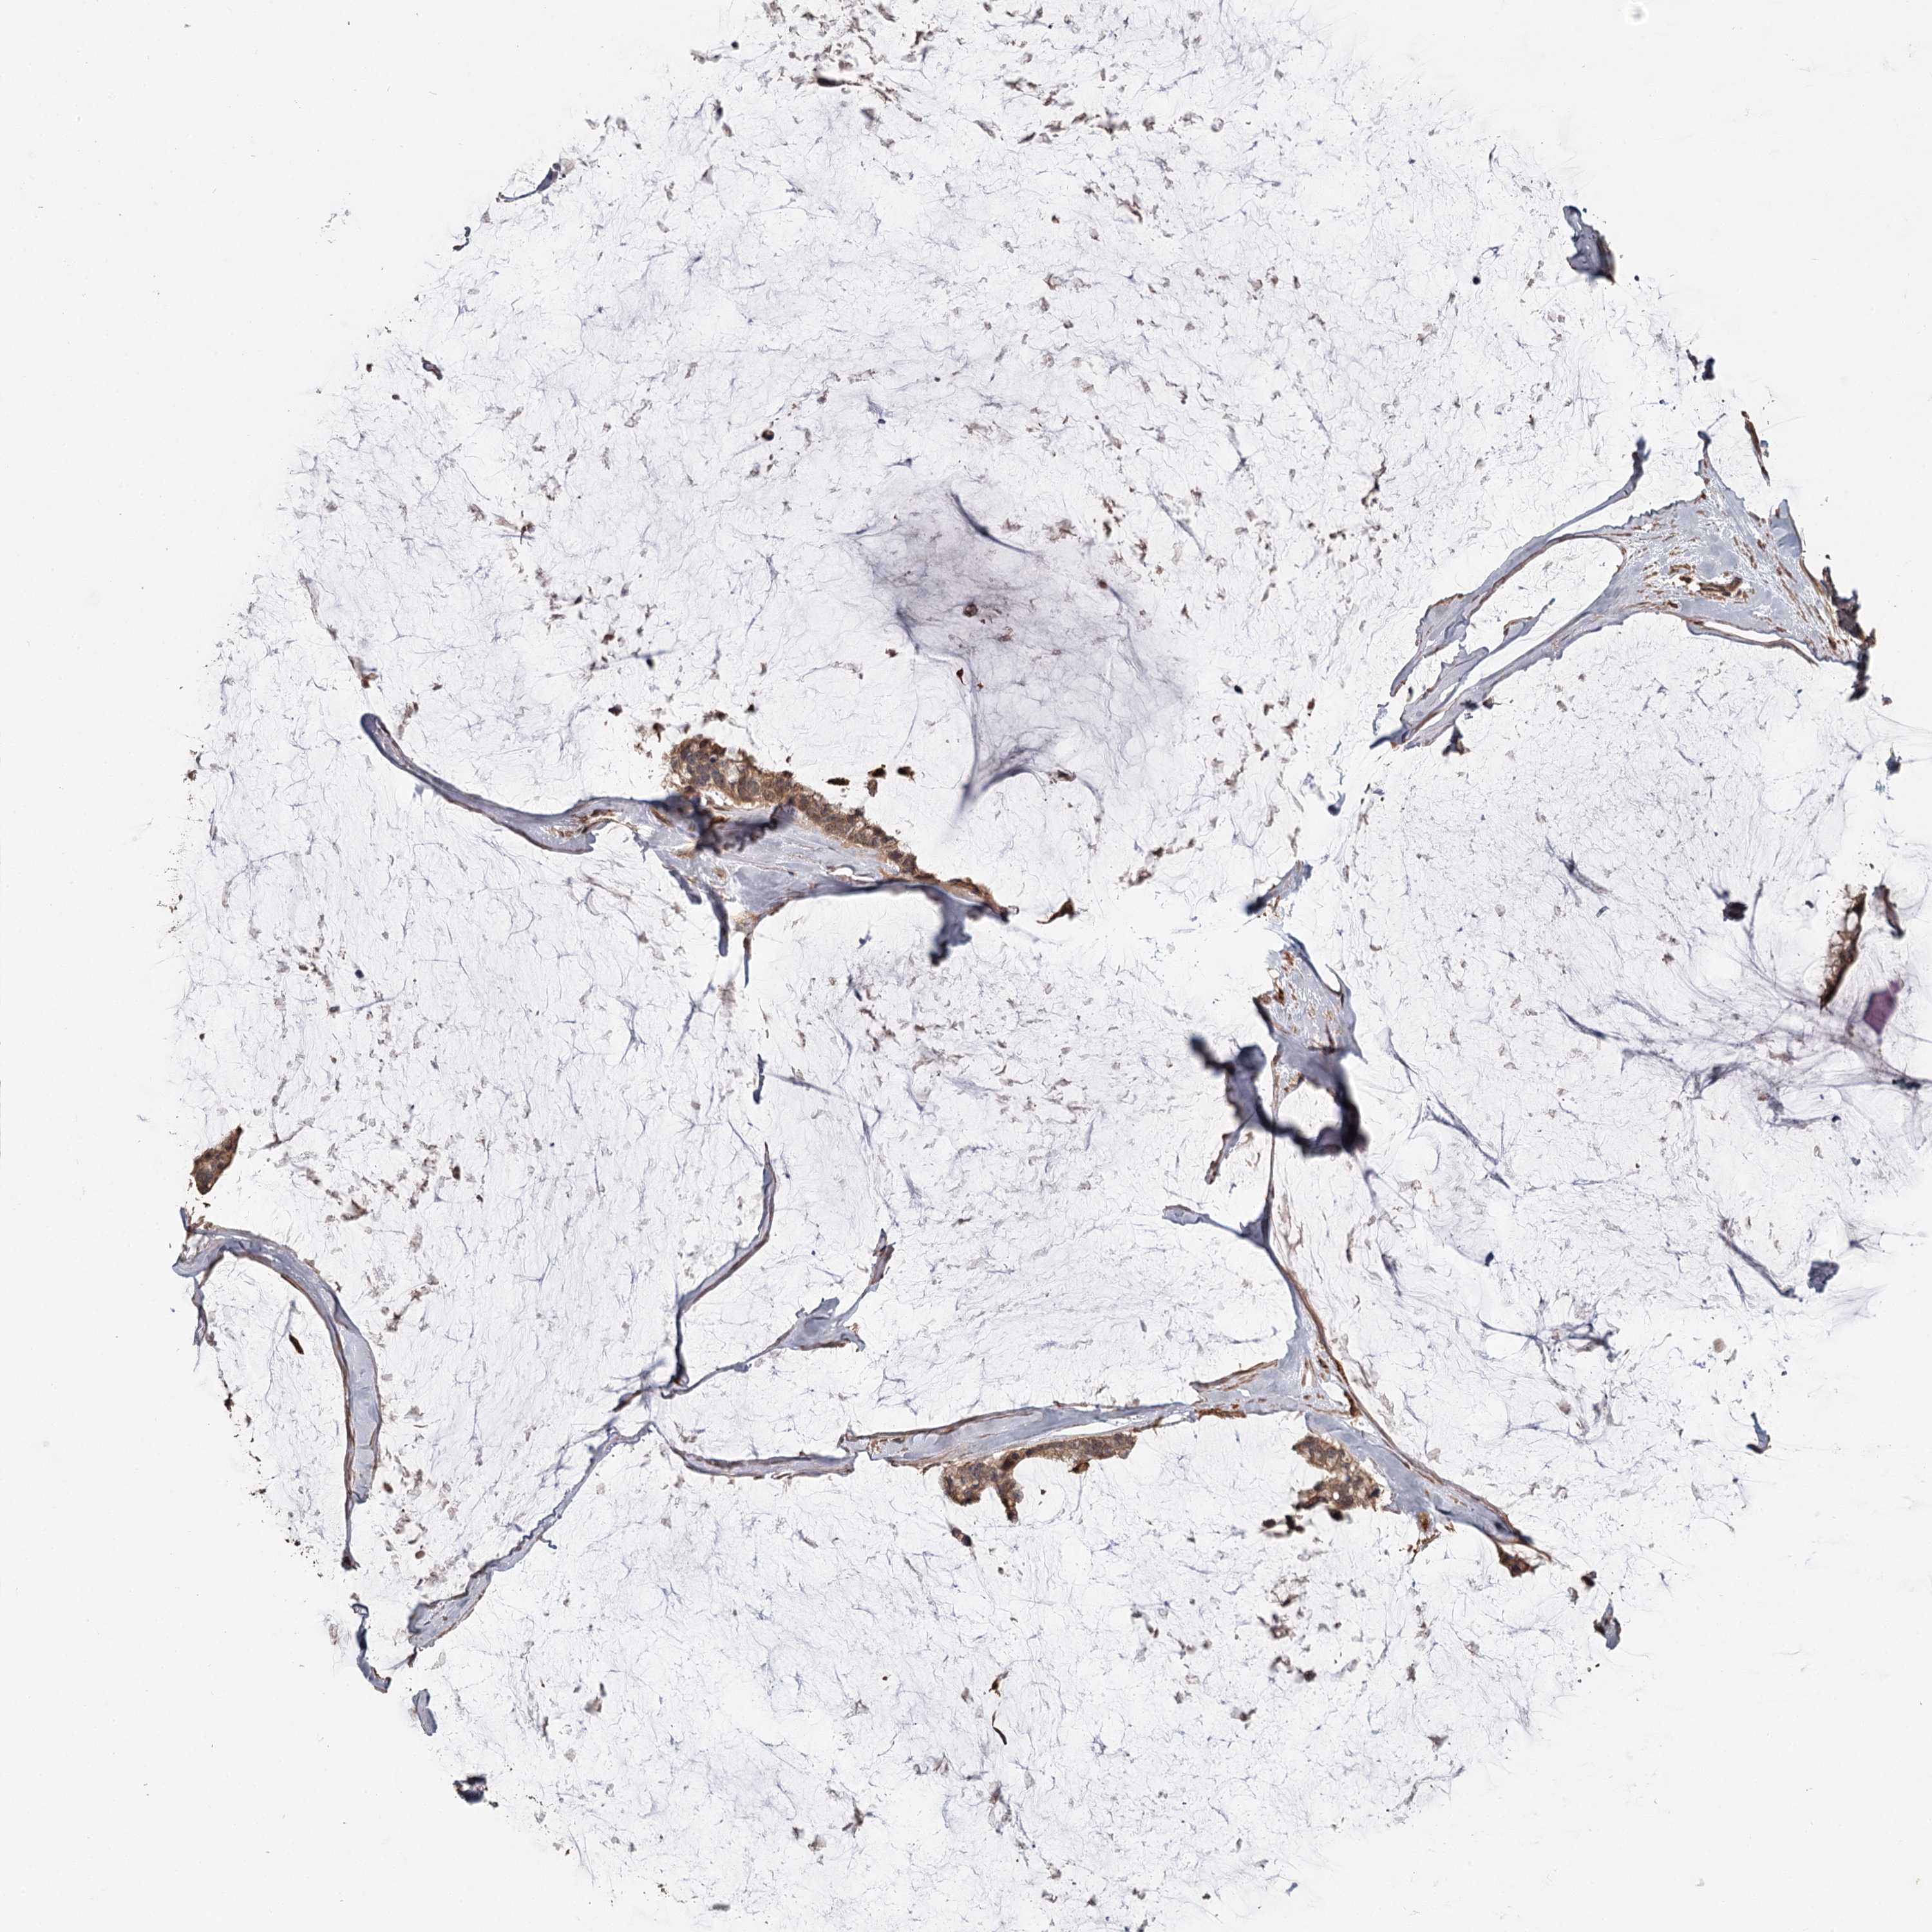

OVARIAN CANCER - Protein expressioni

A mouse-over function shows sample information and annotation data. Click on an image to view it in a full screen mode. Samples can be filtered based on level of antibody staining by selecting one or several of the following categories: high, medium, low and not detected. The assay and annotation is described here.

Note that samples used for immunohistochemistry by the Human Protein Atlas do not correspond to samples in the TCGA dataset.

Antibody stainingi

Antibody staining in the annotated cell types in the current human tissue is reported as not detected, low, medium, or high, based on conventional immunohistochemistry profiling in selected tissues. This score is based on the combination of the staining intensity and fraction of stained cells.

Each image is clickable and will lead to virtual microscopy that enables deeper exploration of all samples and also displays staining intensity scores, fraction scores and subcellular localization as well as patient and tissue information for each sample.

Antibody HPA039106

Cystadenocarcinoma, serous, NOS

Carcinoma, endometroid

Cystadenocarcinoma, mucinous, NOS

Carcinoma, NOS